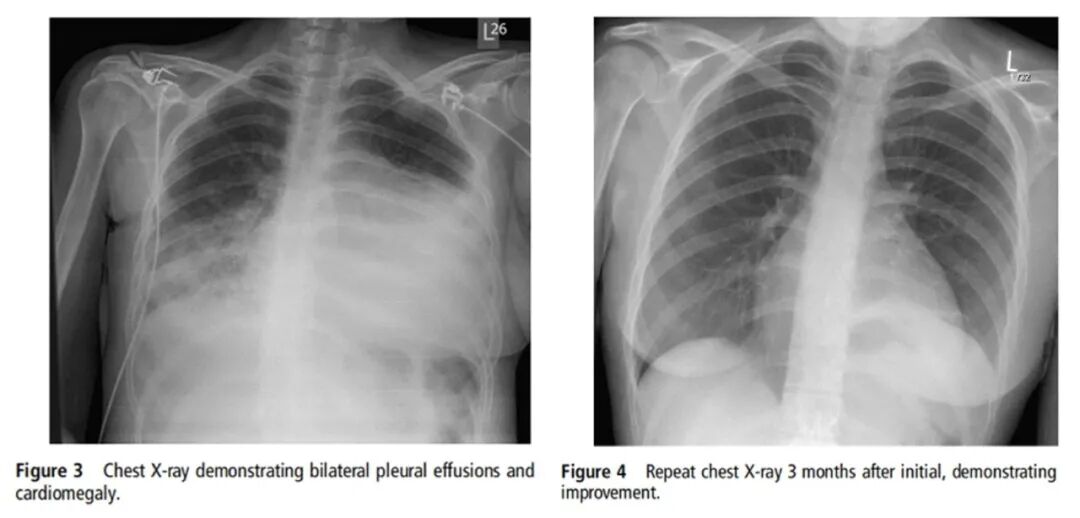

21岁青年女性。主诉:腹痛、腹泻、呕吐2周。既往哮喘病史。实验室化验:血嗜酸性粒细胞水平升高。影像学示心包积液及双侧胸腔积液。心脏彩超示左室射血分数35%。抗感染治疗过程中呼吸困难加重,复查X线胸片提示双侧胸腔积液较前加重,予气管插管、放胸水、积极治疗心衰。多系统病变,不除外风湿性疾病,予甲强龙500 mg/d静脉滴注3 d后激素逐渐减量。2周后出现意识障碍,伴癫痫发作3次,头CT、腰穿、脑电图正常,头颅磁共振和血管造影显示深层白质变化,与脑血管炎一致。考虑为ANCA阴性EGPA,应用激素联合环磷酰胺。治疗3个月后复查X线胸片明显吸收,心脏彩超示射血分数改善。[Tyagi N, et al. BMJ Case Rep, 2015, 2015:bcr2015212511. ]

图片